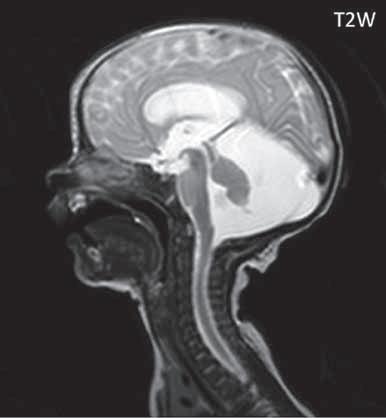

I.1.8 Dandy-Walkerova malformace (D-W variant, D-W komplex, D-W spektrum )

V současné odborné literatuře je nejčastěji užíván termín D-W spektrum, který snad nejlépe vyjadřuje velmi široké možnosti vrozených změn zadní jámy lební. Mezi tuto skupinu cystických malformací zadní jámy lební pak řadíme klasickou malformaci D-W a její varianty, mega cisterna magna, arachnoidální cystu zadní jámy lební a retrocerebelární vak (Blake’s pouch cysta). Zařazení malformace do určité klinické jednotky není někdy jednoznačné, proto je možná výhodnější a přesnější vycházet z přesného popisu zobrazených změn. Příčina D-W malformace není známa, nabízejí se dvě hypotézy: 1. nepropustná spodina IV. komory, eventuálně uzávěr nebo pozdní otevření otvorů, kterými proudí likvor ze IV. komory. 2. primární hypogeneze mozečku. Embryonální vývoj mozečku ze všech hlavních struktur mozku trvá nejdelší dobu, a proto je velmi vulnerabilní k různým patologickým příčinám po dlouhou dobu svého vývoje.

Zobrazení

D-W malformace je charakterizována hypoplazií vermis mozečku, rozšířením IV. mozkové komory, která se často cysticky vyklenuje dorzálně a může imitovat arachnoidální cystu, rozšířením zadní jámy lební a vysokým úponem tentoria s confluens sinum nad lambdovým švem. Okcipitální kost může být vlivem tlakových změn remodelována, existují i případy s porušením její kontinuity a encefalokélou. Hydrocefalus pozorujeme v 80 %, častá je přítomnost dysgeneze corpus callosum, schizencefalie.

D-W variant byl vyčleněn pro případy, kdy všechny základní příznaky nemusí být plně vyjádřeny nebo může některý zcela chybět. Bývá přítomna hypoplazie mozečku, což je dominantní příznak, IV. komora je obvykle rozšířena, někdy pozorujeme, že tvarem připomíná na axiální řezu „klíčovou dírku“, zadní jáma lební naopak rozšířena nebývá.

Mega cisterna magna je struktura likvorového signálu, lokalizována dorzálně a kaudálně od mozečku, není doprovázena hypoplazií mozečku, rozšířením IV. komory ani hydrocefalem, někdy může být tlakem zeslabená lamina interna lebky v zadní jámě lební. Diferenciální diagnostika mezi mega cisterna magna a arachnoidální cystou je mnohdy obtížná a může nám pomoci CT cisternografie (chybí nebo pozdní pronikání kontrastní látky do arachnoidální cisterny), určité informace může přinést MR vyšetření pulzace likvoru.

Retrocerebelární vak (Blake’s pouch cysta) vzniká embryonálně vyklenutím části stropu IV. komory (velum

mediale superius) do cisterny magna (vak je vyplněn likvorem, chybí foramen Magendii). Je charakterizován rozšířenou a široce otevřenou IV. komorou, která komprimuje bazální cisterny, hypoplazie vermis mozečku naopak není přítomna. Široce komunikující IV. komora (někdy obsahuje choroidální plexus), přičemž komunikace mezi komorovým systémem a subarachnoidálními prostory je pouze přes laterální foramina Luschkae.

Obr. I.1.8a Dandy-Walkerova malformace, rozšířená IV komora (tvar klíčové dírky)

Obr. I.1.8b Dandy-Walkerova malformace, rozšířená IV komora široce komunikující s cisterna magna, hypotrofie mozečku (snímky zapůjčeny z archivu prim doc MUDr M Mechla, Ph D, MBA)

Obr. I.1.8c Dandy-Walkerova malformace, rozšířená IV komora široce komunikující s cisterna magna, hypotrofie mozečku (snímky zapůjčeny z archivu prim doc MUDr M Mechla, Ph D, MBA); stejný pacient jako na obr I 1 8b

Obr. I.1.8d Dandy-Walkerova malformace, rozšířená IV komora široce komunikující s cisterna magna, hypotrofie mozečku, vysoký úpon tentoria (šipka) (snímky zapůjčeny z archivu prim doc MUDr M Mechla, Ph D, MBA); stejný pacient jako na obr I 1 8b, c

Obr. I.1.8e Dandy-Walkerovo spektrum (hypoplazie vermis, IV komora je rozšířená a široce zeje) (snímky zapůjčeny z archivu as MUDr J Lisého, CSc )

Obr. I.1.8f Dandy-Walkerovo spektrum (hypoplazie vermis, IV komora je rozšířená a široce zeje) (snímky zapůjčeny z archivu as MUDr J Lisého, CSc ); stejný pacient jako na obr I 1 8e

Obr. I.1.8g Dandy-Walkerovo spektrum (hypoplazie vermis, IV komora je rozšířená a široce zeje), (snímky zapůjčeny z archivu as MUDr J Lisého, CSc ); stejný pacient jako na obr I 1 8e, f

Obr. I.1.8h Mega cisterna magna

Obr. I.1.8ch Retrocerebelární vak (Blake’s pouch cyst), široce komunikující IV komora, chybí foramen Magendii